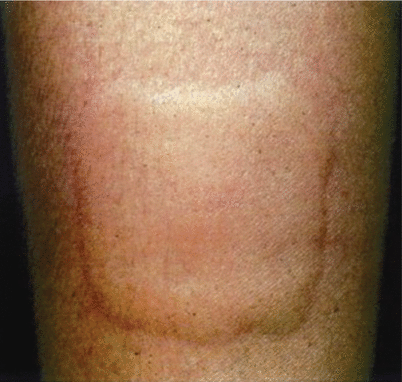

Fig. 27.1

Urticarial lesions (By permission of B Cohen and CU Lehmann, DermAtlas, Johns Hopkins University, 2000–2007)

Clinically, urticarial lesions are intensely pruritic and can appear anywhere on the body, typically appearing quickly and lasting 1–24 h [8]. Unlike other pruritic skin diseases such as atopic dermatitis, patients with urticaria find relief from rubbing the skin versus scratching, making excoriated skin a less common finding in CSU [9]. Lesions can vary in size and can be confluent (see Fig. 27.1). The swelling observed with urticaria results from the movement of plasma from small blood vessels into adjacent connective tissue [4]. Angioedema often coexists with urticaria, and develops from a deeper, swelling of the dermis, subcutaneous, and submucosal tissues. Angioedema is described as painful or burning in quality, and is rarely pruritic [10]. It frequently involves mucous membranes with common locations being the face, lips, tongue, pharynx, and extremities (see Fig. 27.2) [9]. In contrast, urticaria, both acute and chronic, rarely involves mucosal surfaces [10]. Angioedema typically has a slower resolution time than hives, often greater than 24 h and larger areas may take longer to resolve [9, 10].